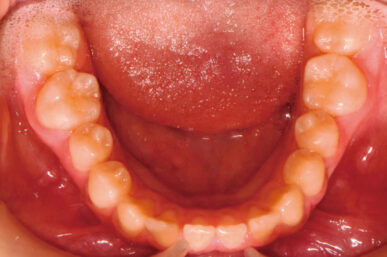

• Before

• After

出っ歯が気になるという事でしたが、下顎がさがっていました。治療開始が遅かったため生え代わりを待つ必要があり、治療期間が長くなりました。

下顎が正しい位置で噛むようになり、出っ歯に見えなくなりました。